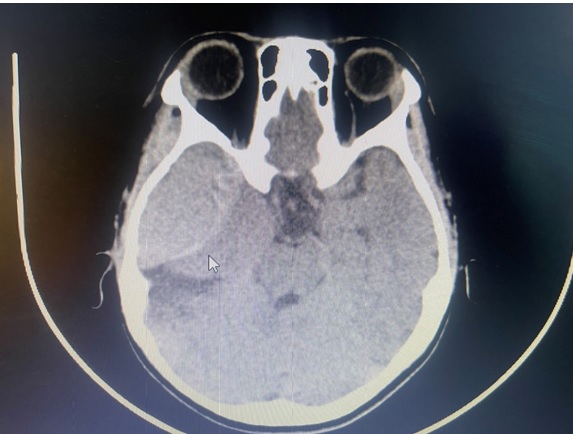

Ngày 22/3/2025, Bệnh viện Đa khoa tỉnh Bắc Ninh tiếp nhận trường hợp bệnh nhân N.T.Y.N (11 tuổi), chấn thương sọ não nặng sau tai nạn giao thông, nhập viện trong tình trạng hôn mê, Glasgow 6 điểm, đồng tử không đều, yếu nửa người trái.

Kết quả chẩn đoán hình ảnh khẩn cấp cho thấy bệnh nhân có khối máu tụ ngoài màng cứng lớn bán cầu phải. Nhận định đây là tình huống cấp cứu ngoại thần kinh nguy kịch, kíp mổ do Ths Hoàng Hải Hòa – Trưởng khoa Phẫu thuật Thần kinh Lồng ngực phụ trách đã tiến hành mở nắp sọ, lấy máu tụ ngoài màng cứng ngay sau tai nạn giao thông khoảng 2 giờ.

Hình ảnh kết quả chụp sọ não bệnh nhân N.T.Y.N

Sau phẫu thuật, bệnh nhi được hồi sức thở máy truyền máu, quá trình theo dõi sau mổ bệnh nhi có dấu hiệu đồng tử phải giãn theo thời gian, được chụp lại 2 lần cắt lớp sọ não kiểm tra phát hiện ổ dập não, tụ máu nhu mô não tiến triển gây phù não đè ép não nhiều( phim chụp trước mổ lần đầu tiên không có- nhận định là tổn thương thứ phát tiến triển). Đội ngũ phẫu thuật quyết định tiếp tục mổ lần thứ hai, tiến hành lấy máu tụ trong nhu mô não, giải phóng vùng tổn thương chèn ép, giải toả não.